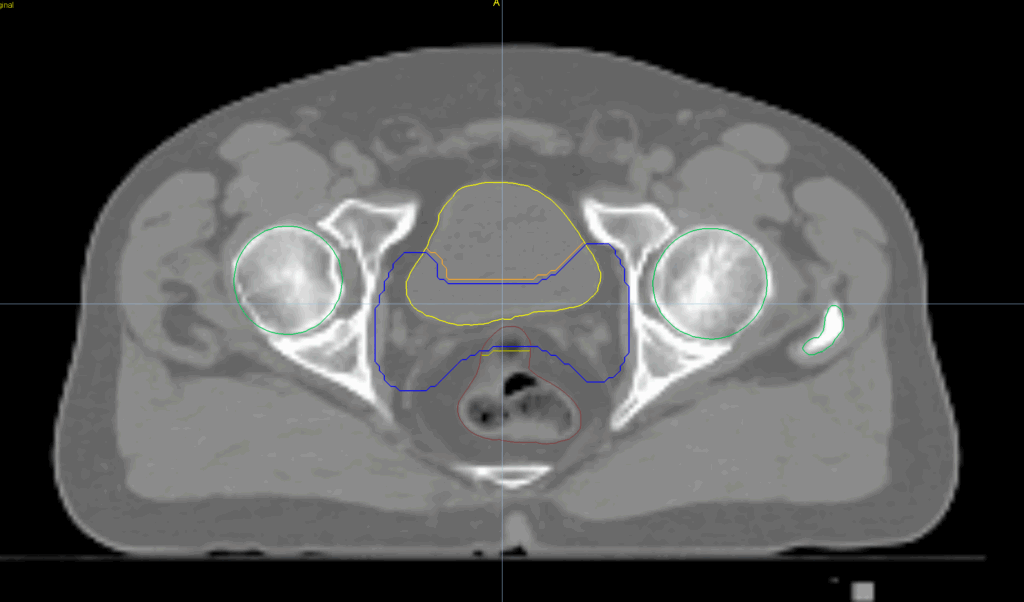

Planning CT Images